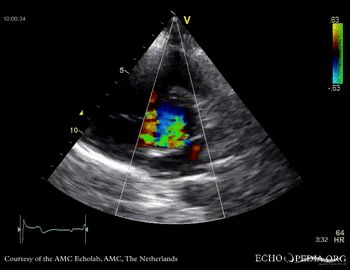

Case 10